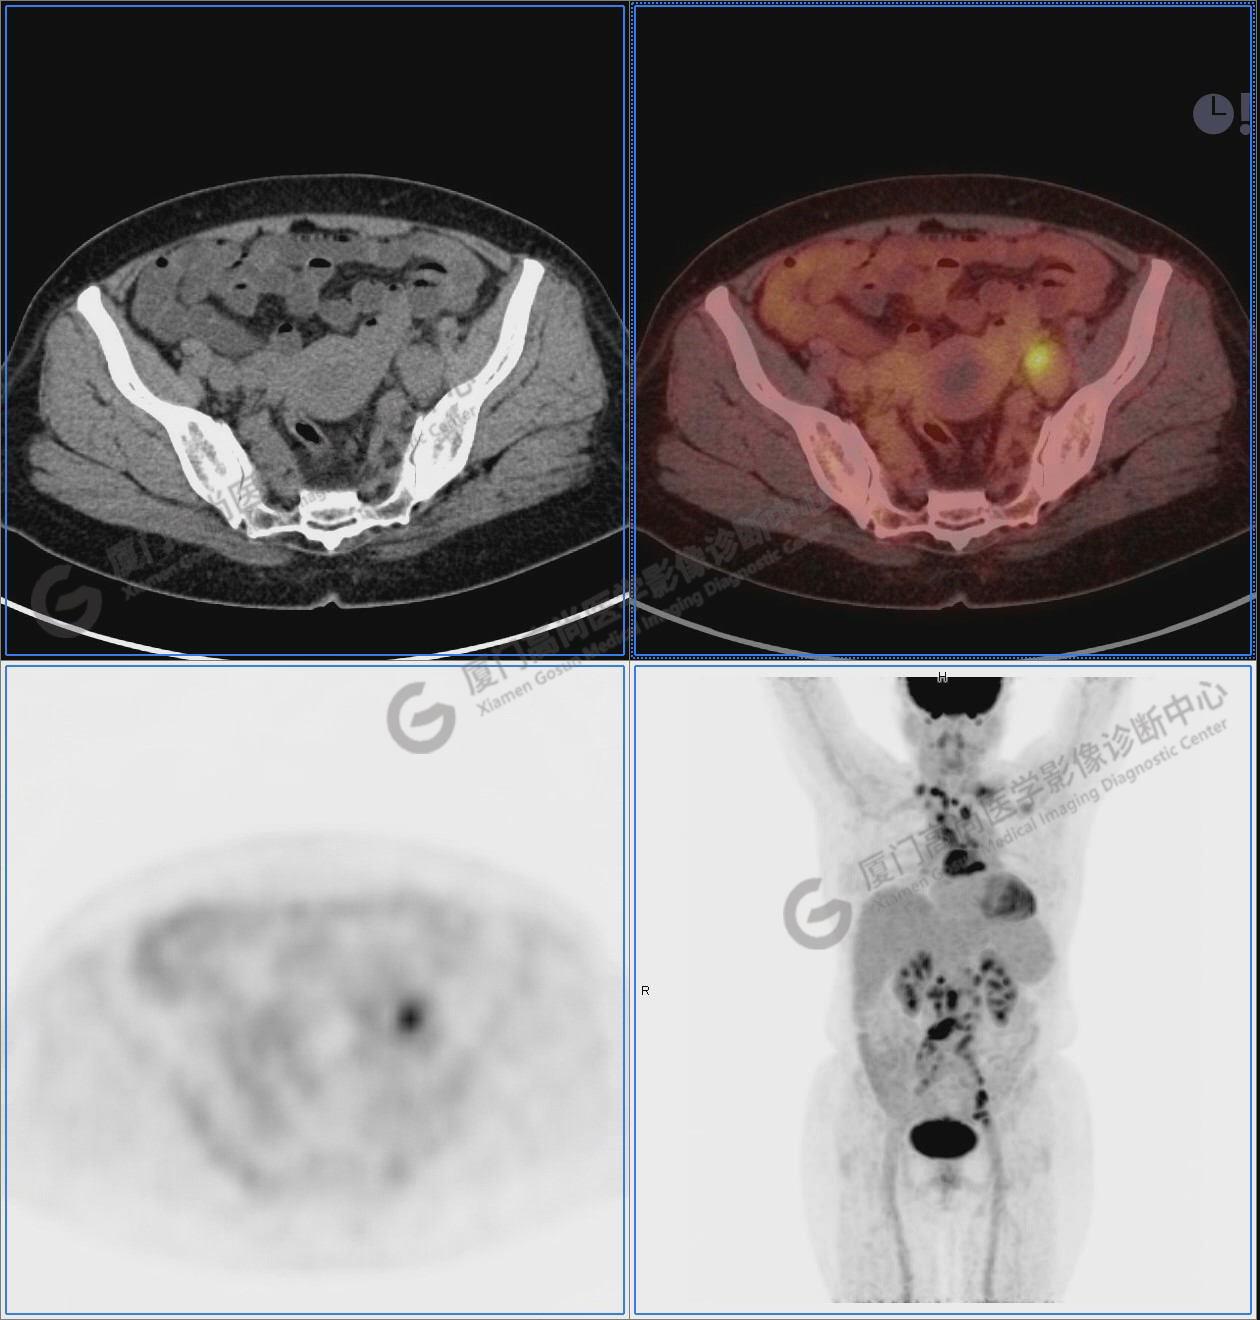

圖1:PET/CT全身圖像

圖2-9:雙側(cè)鎖骨區(qū)、縱隔、右側(cè)內(nèi)乳區(qū)、腸系膜緣、腹膜后、雙側(cè)髂血管旁及盆腔多發(fā)腫大淋巴結(jié)影,代謝不同程度增高,考慮為轉(zhuǎn)移。

圖10-11:子宮頸軟組織腫塊,代謝異常增高,考慮為宮頸癌。

圖12-13:延遲2小時后,宮頸腫塊糖代謝進一步增高。